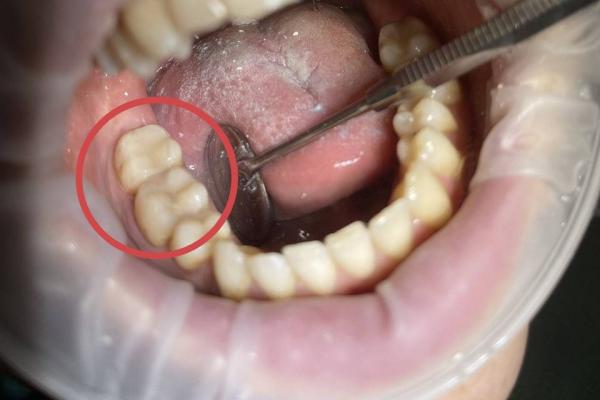

Полный комплекс профессиональной гигиены полости рта включает в себя:

- удаление зубного камня ультразвуком

- удаление пигментированного налета с помощью AirFlow

- полировка зубов профессиональной щеткой и пастой "Kerr super polish"

- покрытие зубов фторосодержащим препаратом